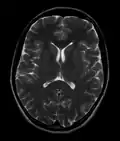

- T2-weighted (T2W) images: CSF is light, but fat (and thus white matter) is darker than with T1. T2-weighted images are useful for visualizing pathology.[26]

Normal axial T2-weighted MR image of the brain -